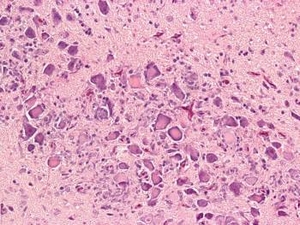

新型ガチョウパルボウイルス(NGPV)は、短いくちばしと矮小化症候群(SBDS)を引き起こします。

ほとんどのアヒルは無症状の感染症を発症しますが、重大な臨床症状を呈したアヒルは、成長遅延、萎縮したくちばし、くちばしの外側に突出した舌、胸腺の腫脹と出血、羽と脚の骨折などを示しました。